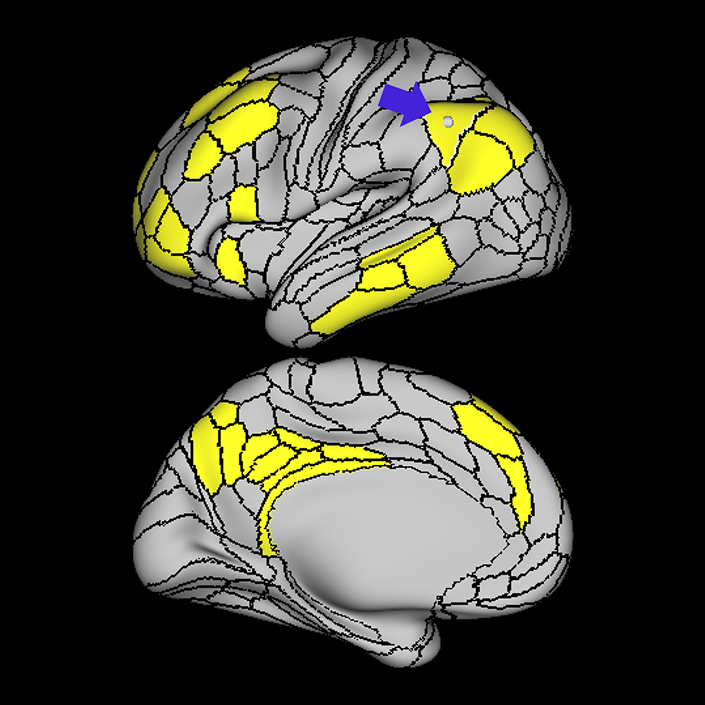

ᐅ SummaryArea SFL: part of the supplementary motor regions. Known to be hemispherically asymmetric. Specifically, the left hemisphere shows more activity when listening to stories and when a participant is matching objects based on a verbal cue. Compared to area 8BL, area SFL shows more activation when listening to a story, matching objects based on verbal cues and in social interaction settings. Compared to area s6-8, area SFL shows more activation in the left hemisphere when individuals listen to a story. In the right hemisphere, area SFL is activated insocial interaction settings and is deactivated during object feature comparison tasks. ᐅ Where is it?Area SFL (superior frontal language area) is located on the posterior medial SFG straddling over the interhemispheric cleft. ᐅ What are its borders?Area SFL borders SCEF inferiorly. Its anterior inferior neighbor is area 8BM and its anterior superior neighbor is area 8BL. Areas 6ma and s6-8 are its lateral neighbors. ᐅ What are its functional connections?Area SFL demonstrates functional connectivity to areas 8BL, 8AV, 9a, 9p, and 9m in dorsolateral frontal lobe, areas 8BM, d32, areas 44, 45, 47L, and 47s in the inferior frontal lobe, area 55b in the premotor areas, areas STSda, STSdp, STSva, STSvp, TE1a, and TGd in the temporal lobe, area PGi in the lateral parietal lobe, and areas 31pv, and 31pv in the medial parietal lobe. ᐅ What are its white matter connections?Area SFL is structurally connected to pyramidal tracts, the frontal aslant tract and contralateral hemisphere. Connections to pyramidal tracts descend through the posterior limb of the internal capsule and cerebral peduncle to the brainstem. The FAT connects SFL with the inferior frontal gyrus, terminating at parcellations 44, IFSp and MI. Contralateral connections course through the body of the corpus callosum to SCEF and 8BL. Local short association fibers connect with SCEF, 8BL, SFL and 6ma. ᐅ What is known about its function?Area SFL was subdivided from adjacent parcellations due to differences in myelin thickness and functional activity. Area SFL is known to be hemispherically asymmetric. Specifically, the left hemisphere shows more activity when listening to stories and when a participant is matching objects based on a verbal cue. Compared to area 8BL, area SFL shows more activation when listening to a story, matching objects based on verbal cues and in social interaction settings. Compared to area s6-8, area SFL shows more activation in the left hemisphere when individuals listen to a story. In the right hemisphere, area SFL is activated in social interaction settings and is deactivated during object feature comparison tasks. |

A: lateral-medial

B: anterior-posterior

C: superior-inferior

DTI image |